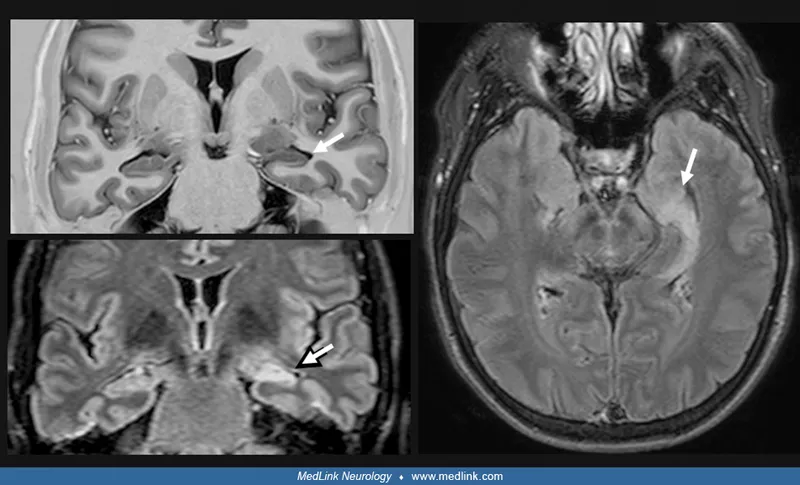

- Normal pressure hydrocephalus (triad: dementia, gait apraxia, incontinence)

- Neuroimaging: MRI brain (or CT if contraindicated)

- Alzheimer's (60%): Gradual memory loss, temporal/hippocampal atrophy

- Vascular (20%): Stepwise decline, stroke history, white matter changes

- Frontotemporal (5%): Personality change, disinhibition, frontal atrophy